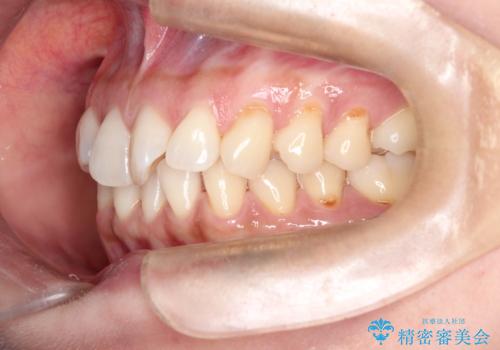

前歯のがたつきと隙間の矯正 インビザラインにて

- 上顎の前歯のがたつきと、下の前歯の隙間を主訴に来院されました。

下の前歯が先天的に欠損していました。

上顎の歯と歯の間をわずかに削りスペースを作り、ガタガタの改善し、下顎の前歯は隙間を閉じる計画としました。

非常に協力的な患者様でしたので、早期に治療が終了することができました。